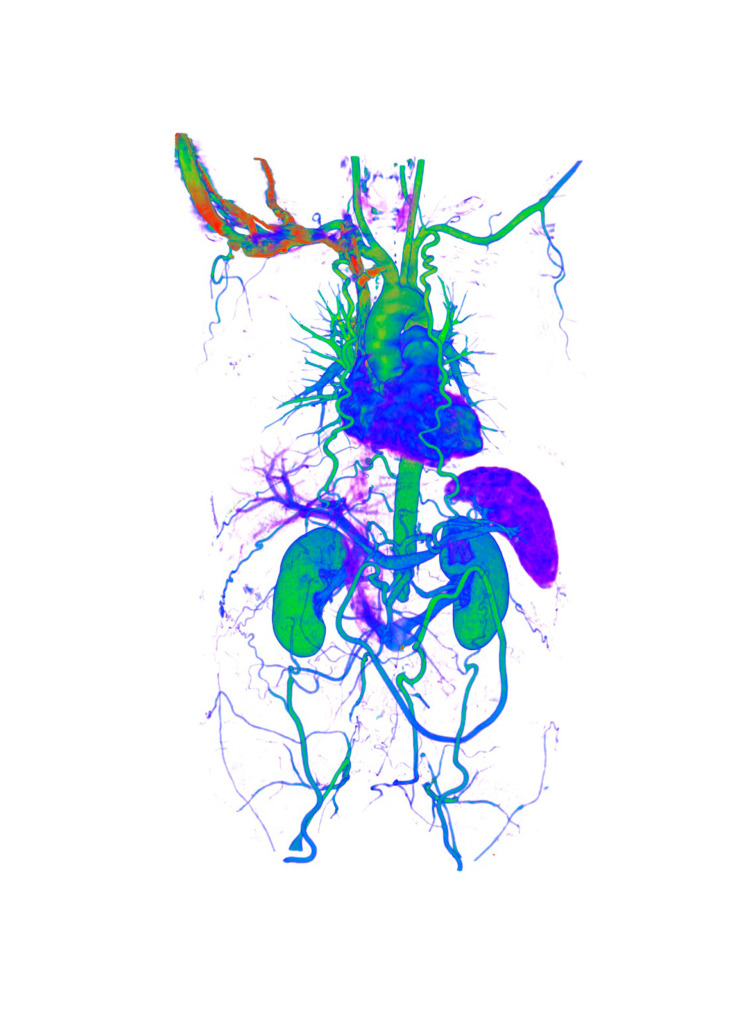

No. Tissues with different densities are best suited to visualisation by CT imaging.

Lungs and heart, bones and muscles or organs injected with a contrast agent reveal the best structure and anatomy.

My favourite image is a 3D CT scan of lung airways.

It was one of my first images using a completely redesigned tissue density colour table. Green is the most dense tissue (bone) and purple is the least dense tissue (lung).

Combining these colours resulted in an extremely bright artistic image.